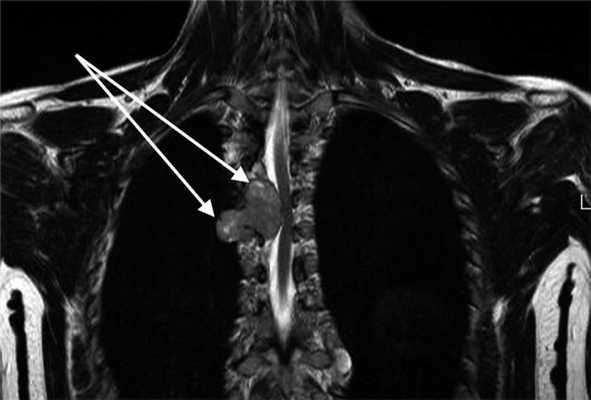

Рис. 2. Магнитно-резонансные томограммы пациента с апикальной нейрогенной опухолью, проникающей в межпозвонковое отверстие.

а — фронтальный срез, б — сагиттальный срез (опухоль указана стрелкой).

При апикальных (цервико-медиастинальных) опухолях (рис. 2) выбор хирургического доступа осуществляли в зависимости от размера опухоли, ее локализации, связи с магистральными сосудами и окружающими структурами. При расположении >50% объема опухоли в плевральной полости (средостении) и небольших ее размерах (до 5 см), удаление производили посредством ВАТС по описанной выше методике.

При опухолях верхней апертуры (цервико-медиастинальные опухоли), исходящих из ветвей плечевого сплетения и с локализацией >50% ее объема на шее (рис. 3), операцию начинали с надключичного доступа.

Рис. 3. Магнитно-резонансная томограмма пациента с цервико-медиастинальной нейрогенной опухолью, проникающей в средостение через верхнюю апертуру, фронтальный срез.